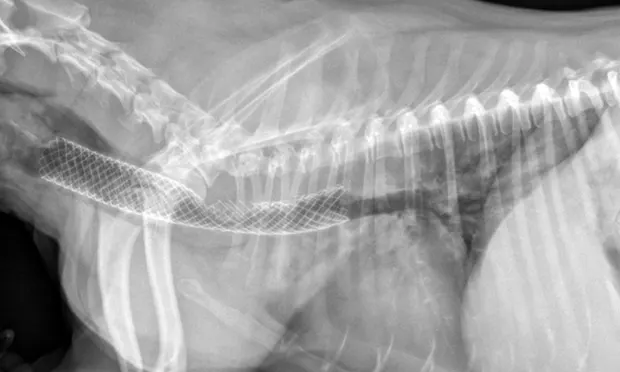

Many surgeons prefer intraluminal stents because they can be noninvasively placed in the cervical or thoracic trachea, reducing risk for complications and shortening anesthetic times. Vet Stent–Trachea is a woven, reconstrainable, self-expanding, nitinol stent3-8 (Figure 3). Nitinol, a nickel–titanium alloy, has thermal shape memory, super elasticity, and elastic hysteresis; the latter minimizes outward force on the interior lumen of the trachea, regardless of stent size.24 The undeployed intraluminal stent is secured within a low-profile delivery system that has radiopaque markers to facilitate positioning. As it is released from the catheter, the stent expands to meet the internal wall of the trachea, foreshortening as it increases in diameter. Because the stent is reconstrainable, it can be pulled back into the delivery system for repositioning after partial release.

Fully deployed stent. Courtesy of Infiniti Medical.

Partially deployed stent. Courtesy of Infiniti Medical.